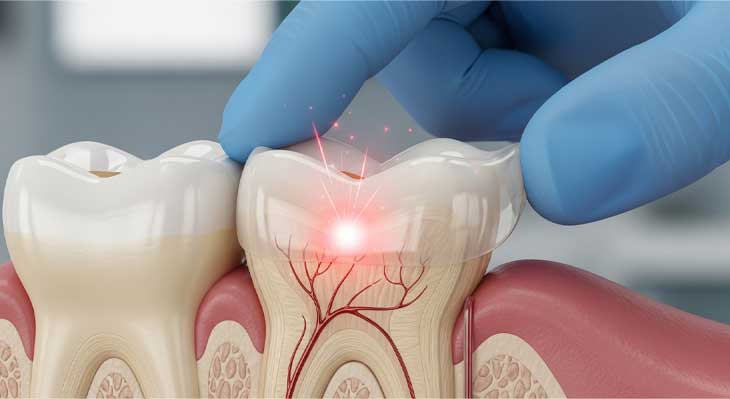

دندان عقل چیست؟

دندان های عقل، یا دندان های مولر سوم، آخرین مجموعه از دندان های دائمی بزرگسالان هستند که ظاهر می شوند و معمولاً بین سنین ۱۷ تا ۲۵ سالگی در دهان رشد می کنند. با این حال، دندان های عقل همه افراد در موقعیت صحیح رشد نمی کنند که می تواند منجر به ایجاد مشکل در رویش آنها شود. برای آگاهی از اینکه دندان های عقل شما در چه وضعیتی قرار دارند مراجعه به یک دکتر دندانپزشک خوب در تهران یا محل زندگی تان و معاینه کامل دندان ها ضروری است. در ادامه با ما همراه باشید تا در مورد انواع دندان عقل و علائم و نشانه های هر یک بیشتر آشنا شوید.

انواع دندان عقل

در یک دسته بندی کلی دندان عقل به سه دسته اصلی تقسیم میشود: روییده، نهفته و نیمه نهفته.